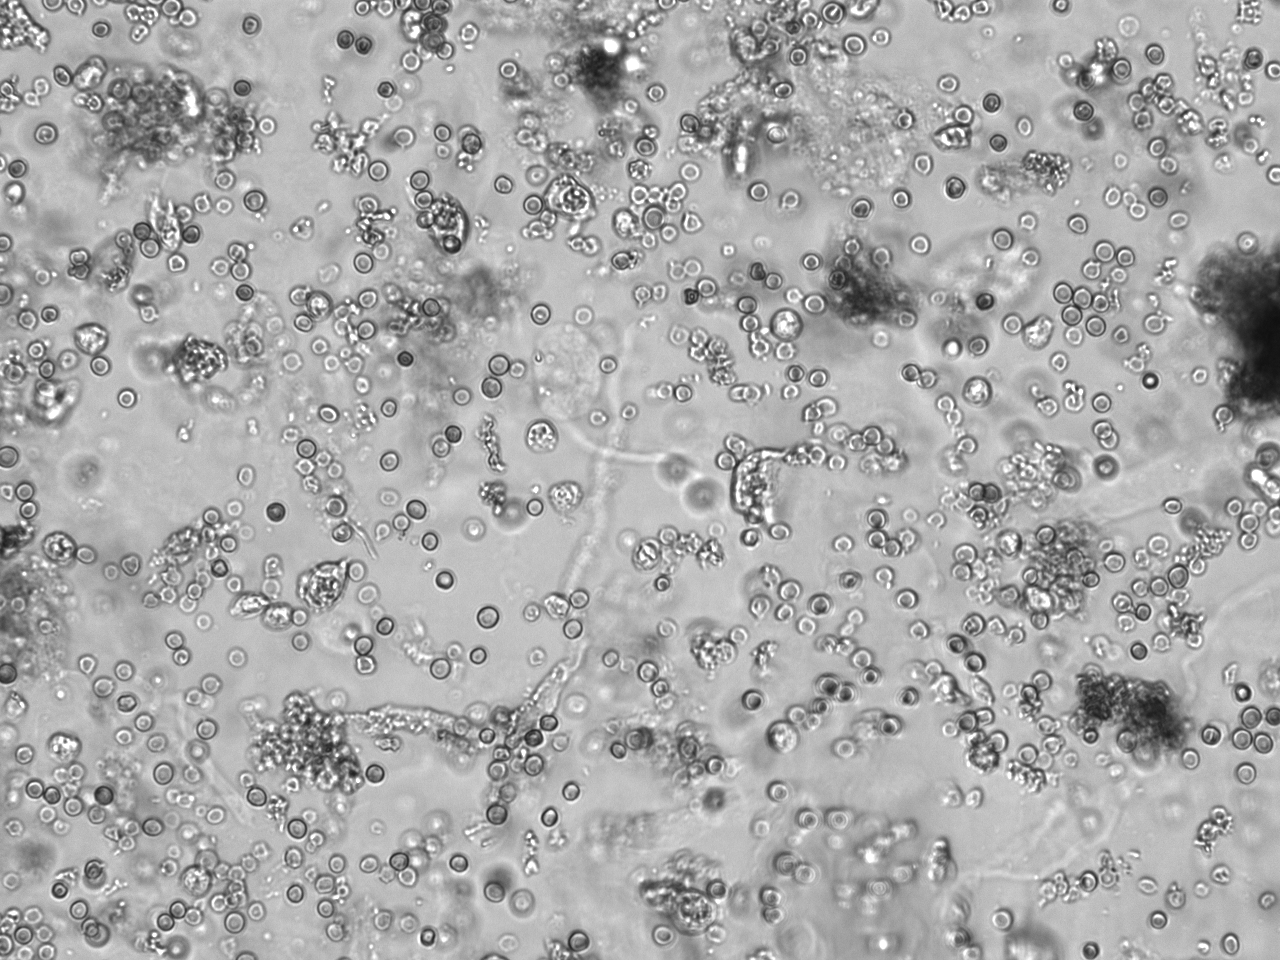

2. Mikroskopische Sedimentanalyse – Zellerkennung und Differenzierung

Die mikroskopische Untersuchung des Urinsediments gibt Aufschluss über zelluläre Bestandteile, die auf eine HWI hinweisen:

- Leukozyten: Vermehrtes Auftreten als Zeichen einer Entzündung

- Erythrozyten: Hinweis auf Hämaturie, die bei schweren Infektionen auftreten kann

- Bakterien: Nachweis von Erregern, vor allem bei frischen Mittelstrahlproben

- Epithelzellen: Plattenepithelzellen können eine Verunreinigung der Probe anzeigen

- Zylinder: Granulozytäre Zylinder deuten auf eine Pyelonephritis hin

Unten ein Beispielbild für ein Harnsediment mit viele Erythrozyten (kein HWI).